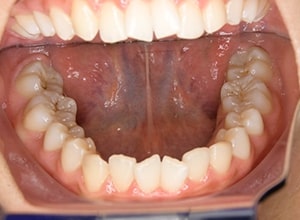

| 口腔内所見 | over jet 3.5mm,over bite4.0mm、下顎正中右側偏位2.0mm、大臼歯関係は左側Ⅰ級であったが、右下6は右下E早期喪失のため近心傾斜しておりⅢ級の臼歯関係となっていた。また上下顎前歯は軽度の叢生を呈していた。 |

| パノラマ所見 | 右下5は右下6近心傾斜により萌出部位不足が認められた。上下顎8歯胚が確認できた。 |

| 批評・予后 | 右下5及び7の萌出前に右下6を整直させることによって、右下5の自然萌出が可能となり正常咬合への咬合誘導が行えたと思う。 |